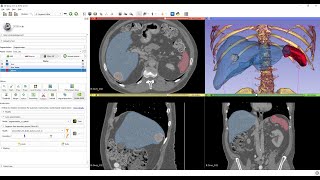

AI assisted segmentation using free tools 3D Slicer and Nvidia Clara video

AI-assisted segmentation using free tools - 3D Slicer and Nvidia Clara

AI-assisted segmentation using free tools - 3D Slicer and Nvidia Clara AI assisted segmentation tutorial using 3D SLICER

AI-assisted segmentation using free tools - 3D Slicer and Nvidia Clara

AI-assisted segmentation using free tools - 3D Slicer and Nvidia Clara AI assisted segmentation tutorial using 3D SLICER